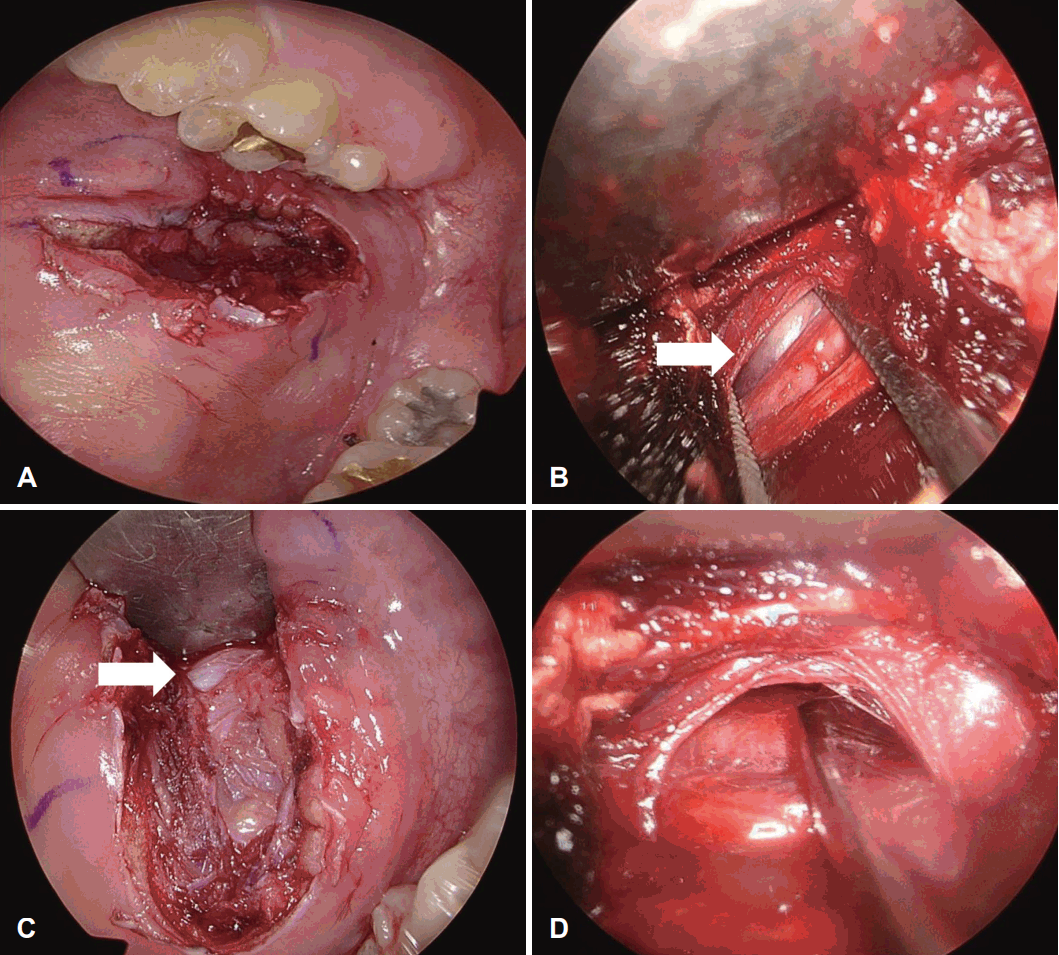

Radiologic Neck CT finding. Red circle indicating enhancing mass lesion in the right anterior parotid gland on axial (A) and coronal view (B).

안면신경 확인을 위해 수술 중 신경 감시장치를 사용하였으며 이하선관의 전방으로 구강 점막과 협근까지 수직 절개를 가하였다(Fig. 2A). Mosquito forceps을 이용하여 구강 점막 피판을 들어올렸고 이후 0도, 30도 내시경을 삽입하여 수술 시야를 확보하였다. 약 2시간 가량 구강 내 접근을 시도하였으나 전체적인 수술 시야가 좁았고 종괴의 앞 1/4 정도만 노출되었으며 더 넓은 수술 시야를 확보할 수 없었다. 저작근의 윗면으로 박리를 진행하여 종괴를 노출시켰으며(Fig. 2B) 협부 안면신경이 종양의 전방 가운데를 종단해 지나가는 것을 확인하였다(Fig. 2C). 신경 손상을 피해 종괴의 측면으로 박리를 진행하였으나 종괴가 저작근보다 뒤에 위치하여 수술 공간이 술전 예상보다 깊고 멀었다. 이로 인해 시야가 좁아 내시경과 수술 기구들 간의 충돌이 빈번하게 발생했으며 수술자의 왼손은 공간 확보를 위해 저작근을 주로 당기고 있어 우측 한 손으로만 종괴를 박리해야 하는 상황이어서 수술 진행이 어려웠다(Fig. 2D). 좁은 공간으로 인해 보조자는 손으로 뺨에서 종괴를 최대한 앞으로 미는 것 외에 입안에서 주위 구조물을 견인하는 데 도움을 줄 수 없었다. 종괴가 안면신경보다 바깥에 위치하고 있었기 때문에 안면신경을 내측 아래 방향으로 밀면서 종괴를 박리하려 했으나 좁은 수술 공간으로 신경을 분리할 수 없었다. 안면신경 손상의 위험성이 높다고 판단하여 수술 중 보호자에게 상황을 설명한 후 동의 하에 외부 접근법으로 수술을 변경하였다. 종괴의 전방 1/4은 박리되어 있었기 때문에 이하선의 앞 경계에서 안면신경을 먼저 찾으면 종괴가 노출될 수 있었기에 광범위한 피부 절개 없이 전이개 절개로 수술을 진행하였다. 절개 후 superficial muscular aponeurotic system (SMAS) 층을 박리하여 이하선의 앞 경계를 노출하였다. 앞 경계에서 종괴는 이하선과 명확하게 분리되어 있지 않았고 이하선 실질 조직과 일부분이 닿아 있었다. 종괴의 후방 60% 둘레가 이하선 조직이었으며 전방 40%는 연조직으로 이루어져 있었다. 협부 안면신경은 종괴의 위에서부터 시작해 종괴의 내측면으로 가로질러 지나가고 있었다. 특히 종괴의 위 경계는 종괴의 피막이 주변 조직과 다소 단단히 유착되어 있어서 단순히 밀거나 당기는 힘으로는 종괴를 박리할 수 없었다. 안면신경의 협측 분지가 종괴 피막에 유착되어 있는 소견이 확인되어 신경 감시장치를 통해 절삭기로 보존하여 분리하였다. 수술 후 시행한 병리조직검사에서 최종적으로 다형선종이 진단되었으며 환자는 안면마비 등의 합병증 없이 약 1년째 경과 관찰 중이다.